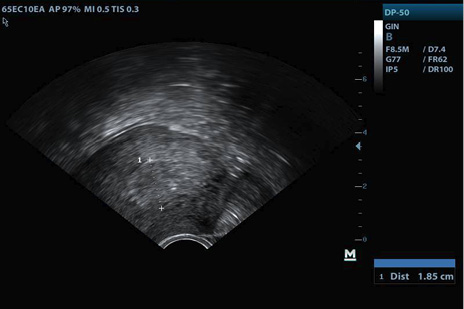

La evolución en controles subsiguientes evidenció persistencia del sangrado genital y dolor pélvico, sin signos de infección, endometrio ecográficamente mixto sin disminución de grosor (Figuras 2-3), y niveles de GCH en descenso lento, por lo que a los 28 días después de la expulsión se decidió prueba terapéutica con misoprostol dosis única vaginal, sin éxito.